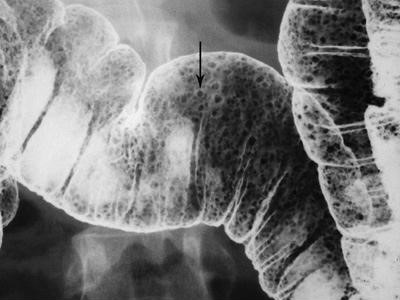

Các u tuyến có sự thay đổi lông nhung mao mức độ cao gọi là u tuyến lông nhung. Chúng là một dạng đặc biệt vì có nguy cơ thoái biến ác tính cao hơn các u tuyến ống hoặc u tuyến ống-lông nhung. Các u tuyến lông nhung có thể nhận ra trên các ảnh cản quang kép dưới hình các tổn thương polyp có bề mặt lưới hoặc nốt do baryt kẹt giữa các lông của khối u (Hình 7) [4].

Các khối u tuyến lông nhung có thể là các tổn thương chia thùy, phẳng, còn gọi là các tổn thương hình “tấm thảm”, chúng được mô tả là các thay đổi tinh vi ở bề mặt đại tràng, lồi rất ít hoặc không lồi vào lòng đại tràng. Kích thước trung bình của u 4 x 6 cm, thường mọc ở trực tràng, manh tràng, và đại tràng lên. Trên phim cản quang kép nhìn thẳng, các nốt to, nhỏ tụ với nhau thành mảng, phân cách nhau bởi các lưới mảnh đọng baryt (Hình 8) [5]. Khi nhìn nghiêng, tổn thương có bờ không đều, trái với bờ nhẵn của niêm mạc bình thường bao quanh.

Hình 7. Hình cản quang kép nằm ngửa cho thấy khối u tuyến lông nhung ở trực tràng. Tổn thương là khối dạng polyp (các mũi tên) với bề mặt nốt và lưới.

Hình 8. Hình cản quang kép chếch sau phải bộc lộ một tổn thương hình thảm. Chú ý bề mặt hình lưới-nốt của tổn thương (mũi tên) ở manh tràng do baryt lấp đầy các kẽ hở của khối u tuyến lông nhung.